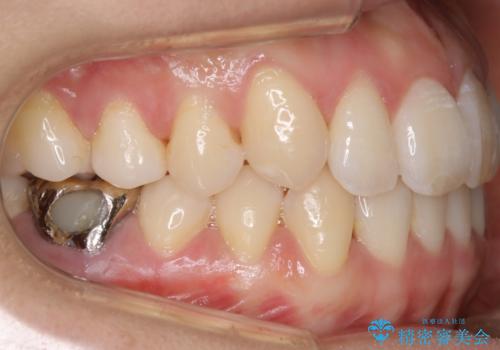

【非抜歯】インビザライン 隠れた前歯を並べる矯正治療

- 前歯のガタつき・奥に隠れてしまっている歯の矯正治療を希望されて初診来院されました。

遠心移動

非抜歯で矯正を行う場合にガタつきの改善に必要なスペースを作るために歯の遠心移動を行います。

最初の位置から奥に歯を移動させていくことで前歯のガタつきを改善したり、前歯の位置を後方に移動させることが可能となります。

その反面、歯の移動距離が大きくなるので治療期間が長くなる傾向があり、その分コントロールの難しさが上がることが予想されます。